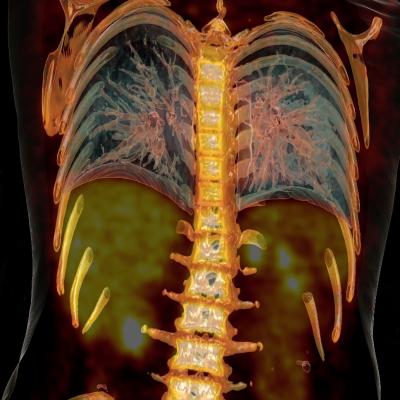

February 23, 2015 — New research from Johns Hopkins School of Medicine reveals a high value for scans which could lead to future change of reimbursement policies for follow-up positron emission tomography/computed tomography (PET/CT) studies in lung cancer. The study, featured in the February 2015 issue of The Journal of Nuclear Medicine, establishes the value of fourth and subsequent follow-up PET/CT scans in clinical assessment and management change in patients with the disease.

In the retrospective study, a total of 1,171 patients with biopsy-proven lung cancer who had positron emission tomography with a radioactive tracer (18F-FDG) were identified at a single tertiary center from 2001 to 2013. Among these, 85 patients (7.3 percent) had four or more follow-up PET/CT scans with a total of 285 fourth and subsequent follow-up PET/CT scans. Median follow-up from the fourth scan was 31.4 months. The follow-up PET/CT scan results were correlated with clinical assessment and treatment changes.

Of the 285 fourth and subsequent follow-up PET/CT scans, 149 (52.28 percent) were interpreted as positive and 136 (47.7 percent) were interpreted as negative for recurrence or metastasis. A total of 47 (55.3 percent) patients died during the study period. PET/CT identified recurrence or metastasis in 44.3 percent of scans performed without prior clinical suspicion and ruled out recurrence or metastasis in 24.2 percent of scans performed without prior clinical suspicion. The PET/CT scan resulted in treatment change in 28.1 percent (80/285) of the patients. New treatment was initiated in 20.4 percent (58/285) scan times, treatment was changed in 5.6 percent (16/285) scan times and ongoing treatment was stopped in 2.1 percent (6/285) scan times.

“Although the value of FDG PET/CT has been established in the follow-up of patients with lung cancer, this study specifically looks at the value of the fourth and subsequent follow-up PET/CT studies, which has not been addressed in any prior studies,” stated Rathan Subramaniam, M.D., Ph.D., lead author of the study. “We now need to establish similar evidence for other human solid tumors,” Subramaniam continued.

The study was performed in the context of the recent Center for Medicaid and Medicare Services declaration that only three FDG PET/CT scans will be covered under section 1862(a)(1)(A) when used to guide subsequent management of anti-tumor treatment strategy after completion of initial anticancer therapy. Coverage of any additional FDG PET/CT scans will be determined by local Medicare administrative contractors.